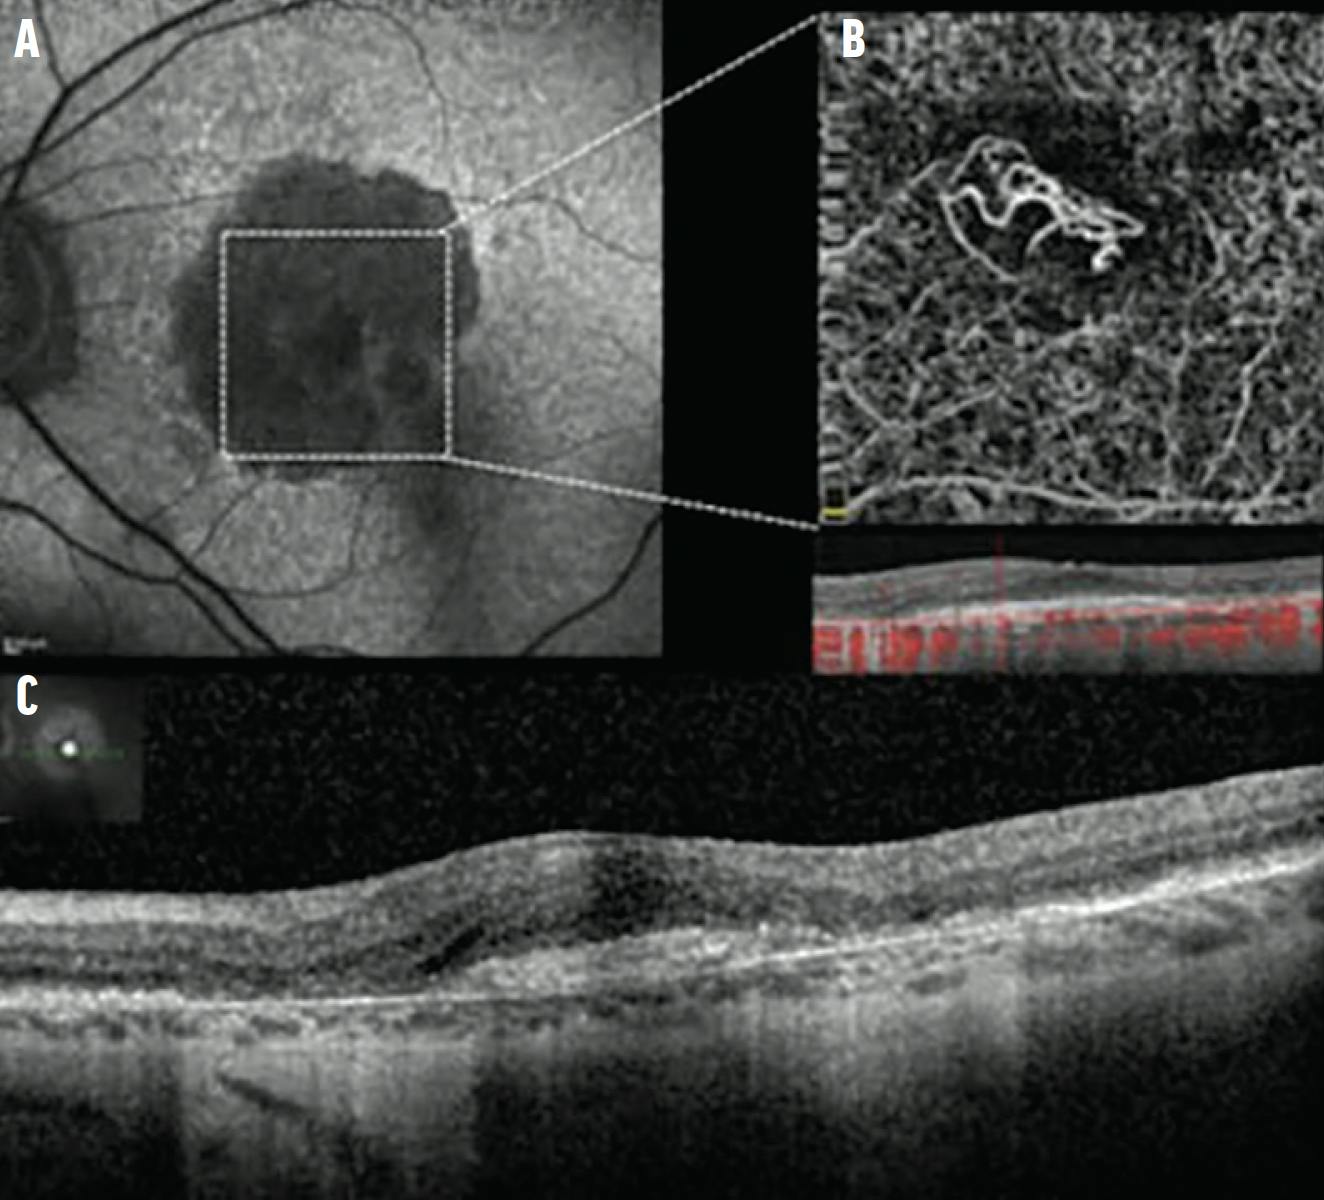

OCTA

OCTA allows us to noninvasively visualize the neovascular network. It is recommended that this test be done in the initial evaluation of all new patients with macular atrophy. In this context, one may find either a “dead tree” network characteristic of an old and inactive neovascularization, or a more “woody” but nonexudative aspect associated with structural OCT (Figure 7), called quiescent neovascularization.14 This type of neovascularization represents a positive prognostic factor for the progression of atrophy. The mechanism suggests that the neovascular loop would be able to feed more RPE and the outer retina. In contrast, quiescent neovascularization switches to an exudative form in about 20% of cases.14

<p>Figure 7. When imaging a mixed lesion (both GA and choroidal neovascularization), FAF shows a “C” shape atrophic lesion (hypofluorescent) with foveal sparing (A). OCTA shows a hyperreflective loop, revealing the choroidal neovascularization (B). The OCT B-scan shows the limits of the GA lesion with a foveal-sparing and hyperreflective lesion in the foveal area (C). No exudation is visible on the OCT B-scan.</p>

Figure 7. When imaging a mixed lesion (both GA and choroidal neovascularization), FAF shows a “C” shape atrophic lesion (hypofluorescent) with foveal sparing (A). OCTA shows a hyperreflective loop, revealing the choroidal neovascularization (B). The OCT B-scan shows the limits of the GA lesion with a foveal-sparing and hyperreflective lesion in the foveal area (C). No exudation is visible on the OCT B-scan.